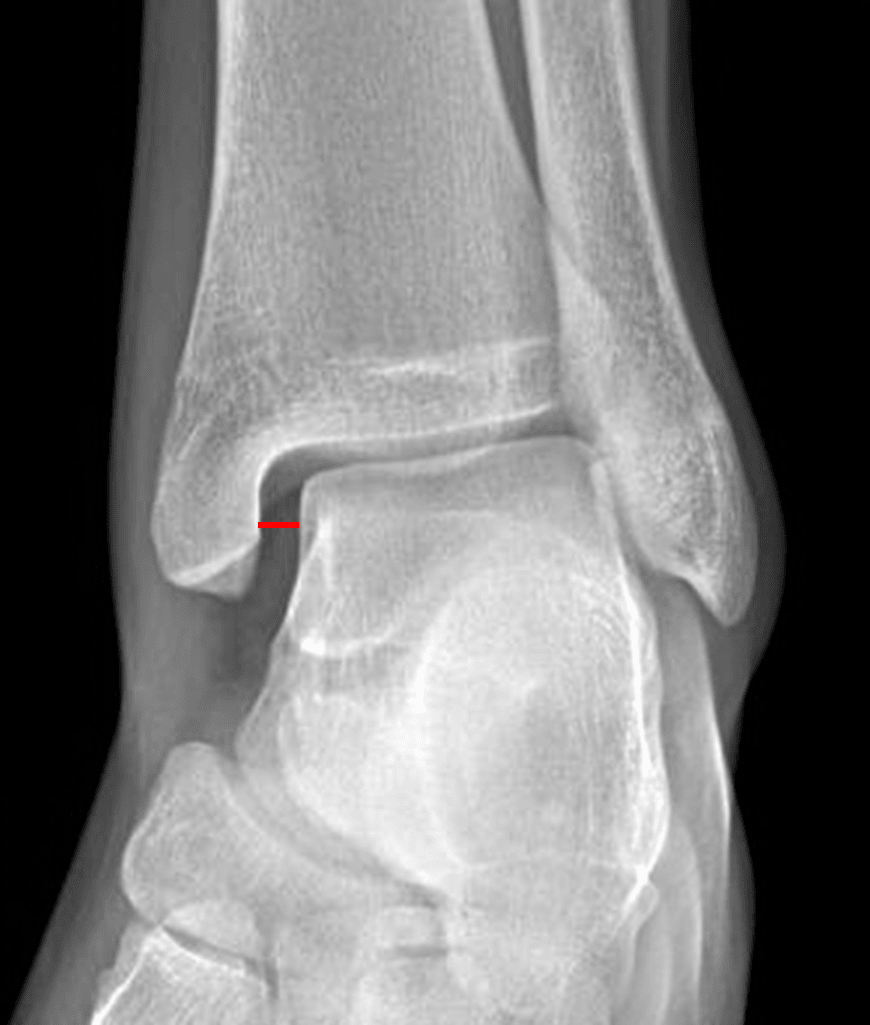

Red line: medial clear space widening concerning for ligamentous injury.